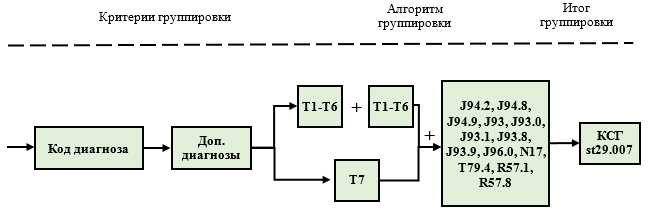

"Группировщик" позволяет каждый случай в реестре пролеченных больных, оплата которого производится в рамках системы КСГ, отнести к определенной группе на основании классификационных критериев, которые соответствуют этому случаю. С помощью данной таблицы осуществляется отнесение случаев ко всем КСГ, кроме КСГ st29.007 "Тяжелая множественная и сочетанная травма (политравма)", алгоритм формирования которой описан в разделе "Особенности формирования отдельных КСГ".